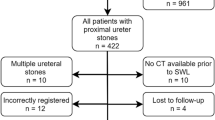

Figure S1 shows the flow diagram of this study. Table 1 shows patient characteristics. There were 1666 eligible patients in the model development cohort and 605 eligible patients in the model validation cohort. The average age was 55.1 years for the development cohort; it was 53.0 years for the validation cohort. Males comprised 75.0% of the development cohort and 81.8% of the validation cohort. The most common diagnosis was upper ureter calculi (61.8% in the development cohort and 59.0% in the validation cohort).

Fig. S1 Flow diagram of the study patients. We obtained the data of patients with upper urinary tract calculi diagnosed by NCCT from 2006 to 2016. After exclusion, we divided the patients into two cohorts according to geographical factors. Finally, we analysed 1,666 patients in the development cohort and 605 patients in the validation cohort (TIFF 223 kb)